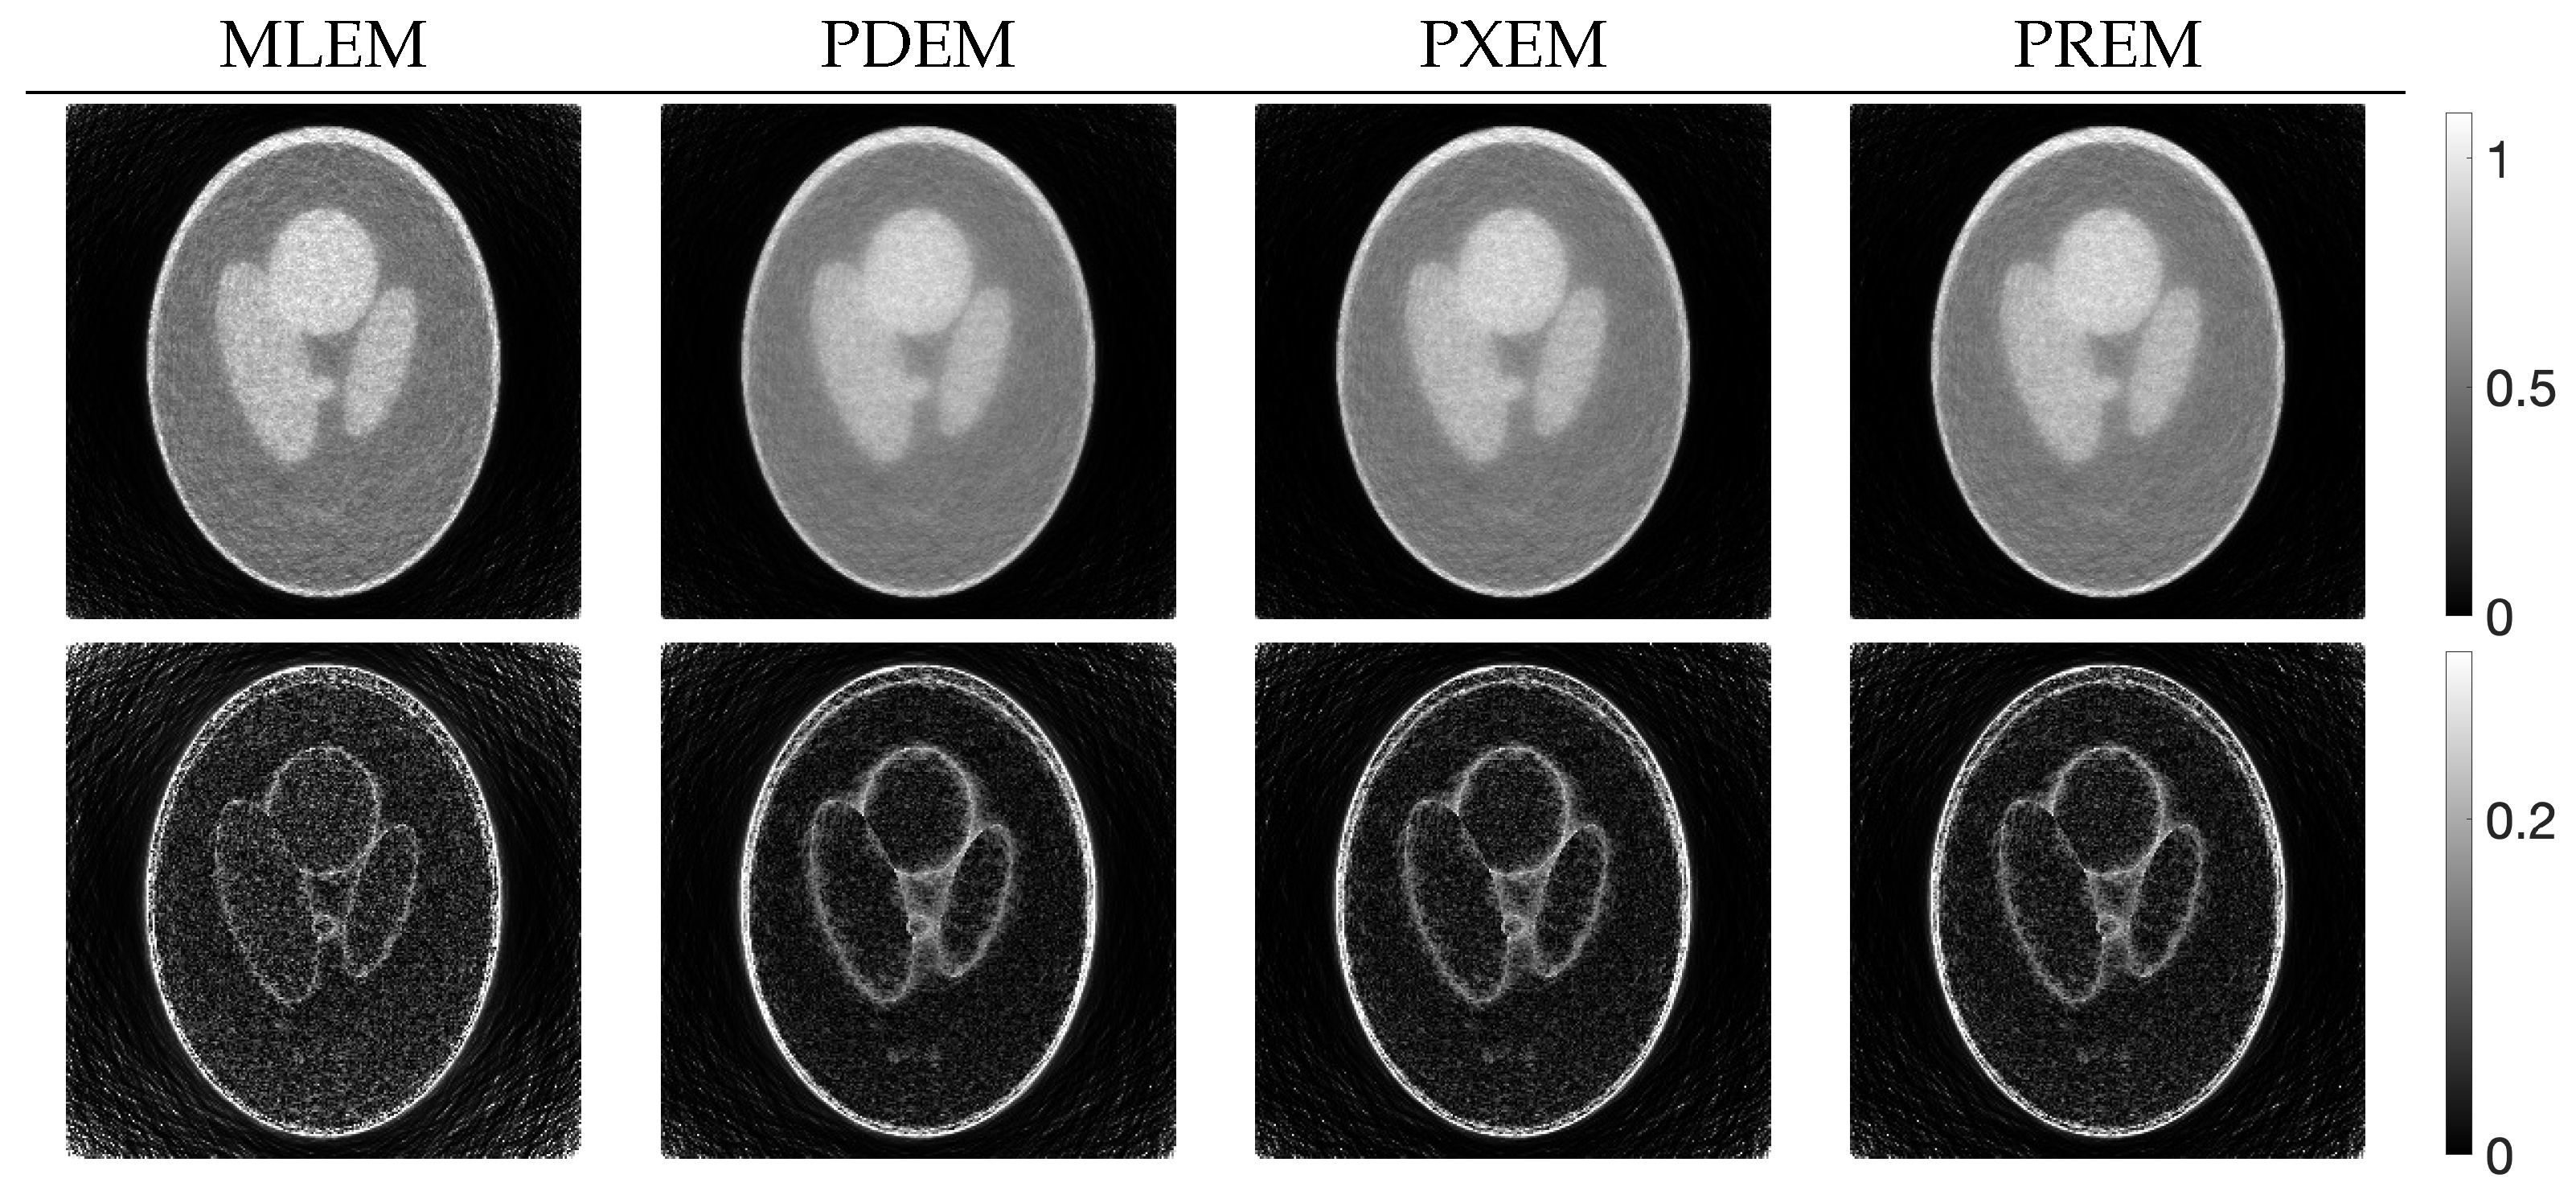

Next, let us examine the results of the physical experiment. The MLEM, PDEM, and PREM methods used the projections shown in the sinogram of Figure 2. The preprocessing time for the parameter estimation in PREM using the reduced-size system was 67 s, which represented an additional 32% of the reconstruction time compared with the original size, which took 207 s. Additionally, Figure 9 plots the changes in the evaluation function and parameters of PREM. Similarly to the numerical experiments, the proposed method operated appropriately. In the transition of the evaluation function, PREM significantly reduced the function value with fewer iterations compared with MLEM and PDEM. The reconstructed images and the density profile are shown in Figure 10 and Figure 11, respectively. The term in the figure denotes the index k on the white horizontal line in the reconstructed image , where . The profile shown in Figure 11, where there are gradual changes in density (in the range of indices from approximately 150 to 500) and sharp transitions (around index 550), indicates that PREM effectively suppressed artifacts caused by noise to a level comparable to PDEM, maintained sharp edges with the same contrast as MLEM, and combined the strengths of PDEM and MLEM.

Figure 10.

Images reconstructed from sinogram obtained from X-ray CT scanner by using MLEM, PDEM, and PREM (the white horizontal lines on the images indicate the positions of the density profiles in Figure 11).